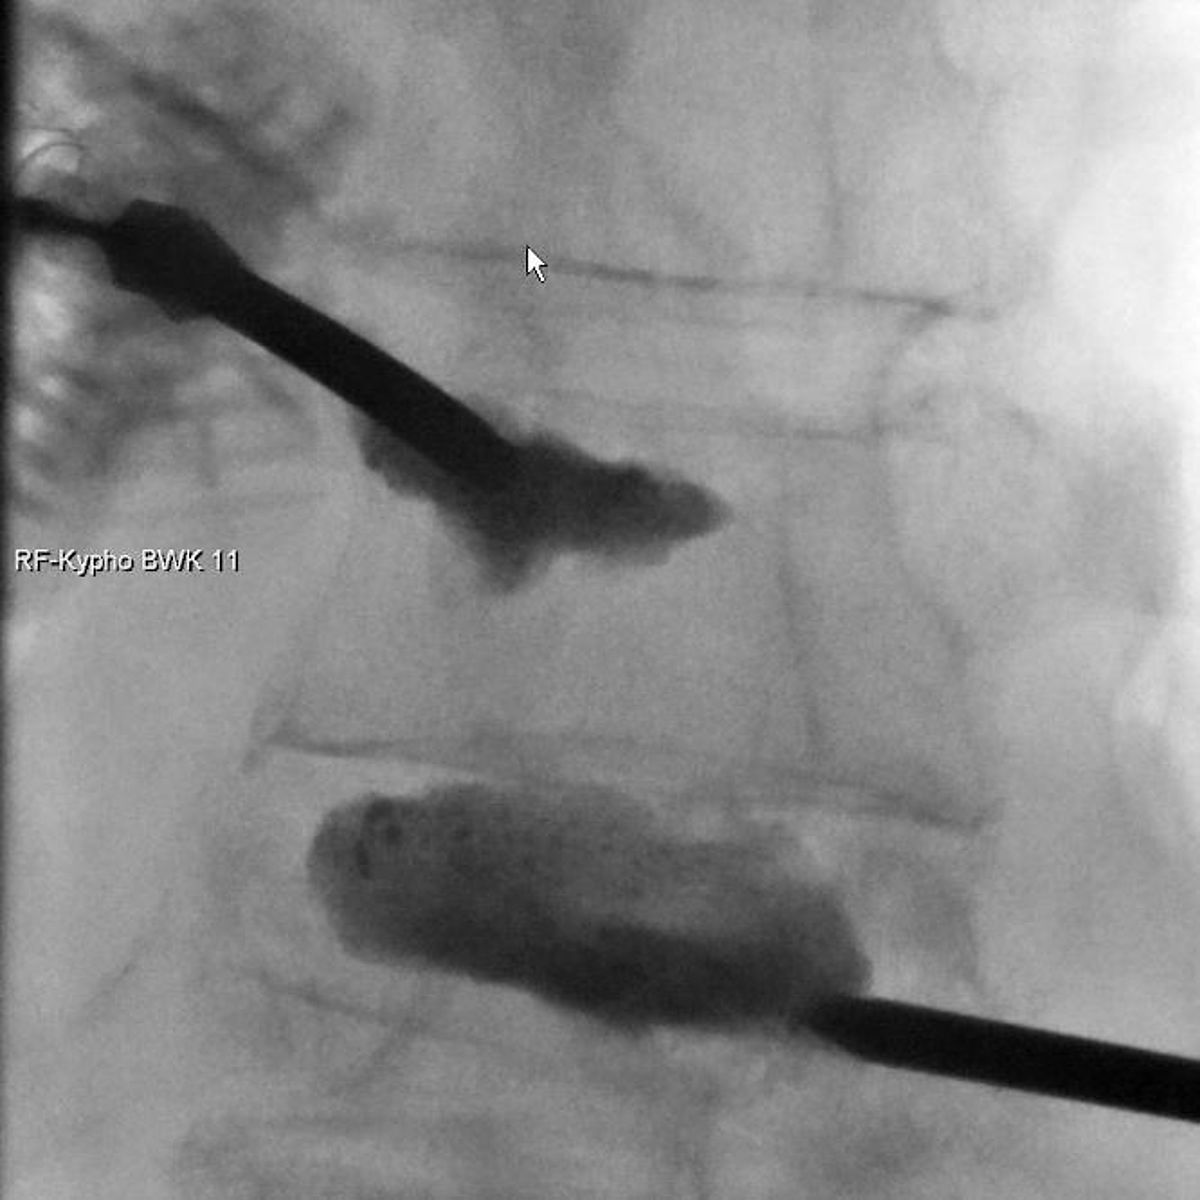

Zur Therapie stehen unsere modernen Großgeräte wie Computertomographen und Durchleuchtungsgeräte (Zwei-Ebenen-Angiographie) zur Verfügung, die schonendes und präzises Arbeiten im Millimeterbereich gewährleisten, was der Sicherheit und der Verbesserung der klinischen Ergebnisse für unsere PatientInnen dient.

- Durchleuchtungsgesteuerte Schmerztherapien

- Kyphoplaste/Vertebroplastie